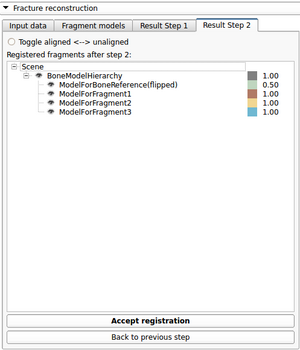

Tutorial and description of panelsUsing the first tab of the loadable module the user should provide the following input data: -3D CT image(volume) of non fractured bone (='Reference image') After providing the input data the 'Initialize reconstruction'-button should be pressed in order to create 3D models of the labelmaps and initialize the reconstruction process If the user wants to provide a better manual interaction the transform sliders (from within the fracture reconstruction) module can be used. Better initialization will decrease the calculation times for the subsequent alignment process and potentially lead to better results. The "Reset manual transform" button to reset the postion of each fragment to the state prior to the manual interaction. After the initialization process is finished the second tab will be opened. The 2D and 3D views will be updated and a surface rendering of the fragments and reference bone will be provided. The user can change colors, opacity and visibility for each single fragment.

After the first step of the reconstruction is finished and user can inspect the intermediate result. 2D and 3D views will be update according to the calculated transformations. At this point the user, the following scenarios are possible: 1) Good registration - Accept registration without performing further registration (fine tuning part will be skipped). By pressing the "Start fine tuning" button the second part of the reconstruction process in which the fragments will be aligned against each other (without using the reference bone) will be started. The parameters for this step can be changed in the corresponding parameter tab ("Parameters for fine tuning") After the calculations for the fine tuning step are finished, the last tab will be opened ("Result step 2"). Again 2D and 3D views will be updated accordingly and the same 4 scenarios as in the previous step are possible.  Updated 2D and 3D views after final step of reconstruction. Note that the visible gaps are due to missing bone that has been "simulated" in this (toy) example. This view was generated using a wireframe representatioin of the fragments in combination with a volume rendering of CT dataset of the (healthy) reference bone